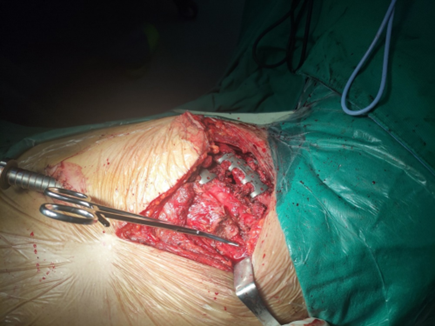

最新的肋骨骨折固定技术,采用的是钢板螺丝固定,无论骨折位于何处,都可以采用合适长度的钢板进行塑形,哪怕是胸骨旁或脊柱旁,也可以将钢板固定在胸骨和脊柱上,用于稳定肋骨。

无需打开肋间肌肉间隙,在肋骨表面就可以让钢板紧密贴合,使患者在术后短时间之内就可以迅速减轻疼痛,正常下地恢复运动。同时还搭配了MIPO微创器械的应用,只需要开10厘米左右的小切口,在胸腔镜辅助下就可以完成多根肋骨骨折的固定,即便是肩胛骨下方的禁区也可以充分固定。